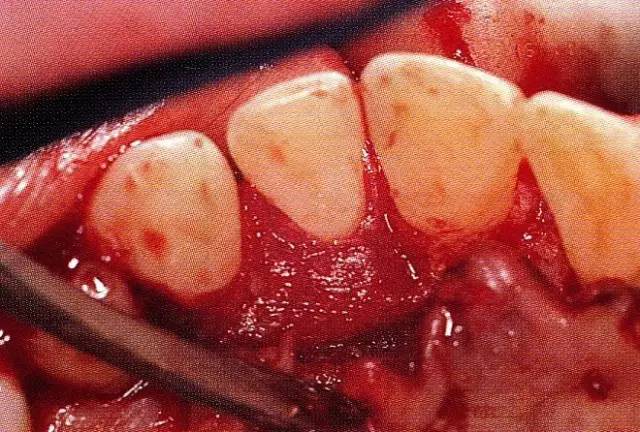

▲圖8-3  進行全厚瓣翻瓣,將根表面的沉積物、骨缺損的肉芽組織徹底清除,確認牙槽骨形態(tài),可看到從頰側(cè)到遠中存在垂直性和水平性的骨缺損。